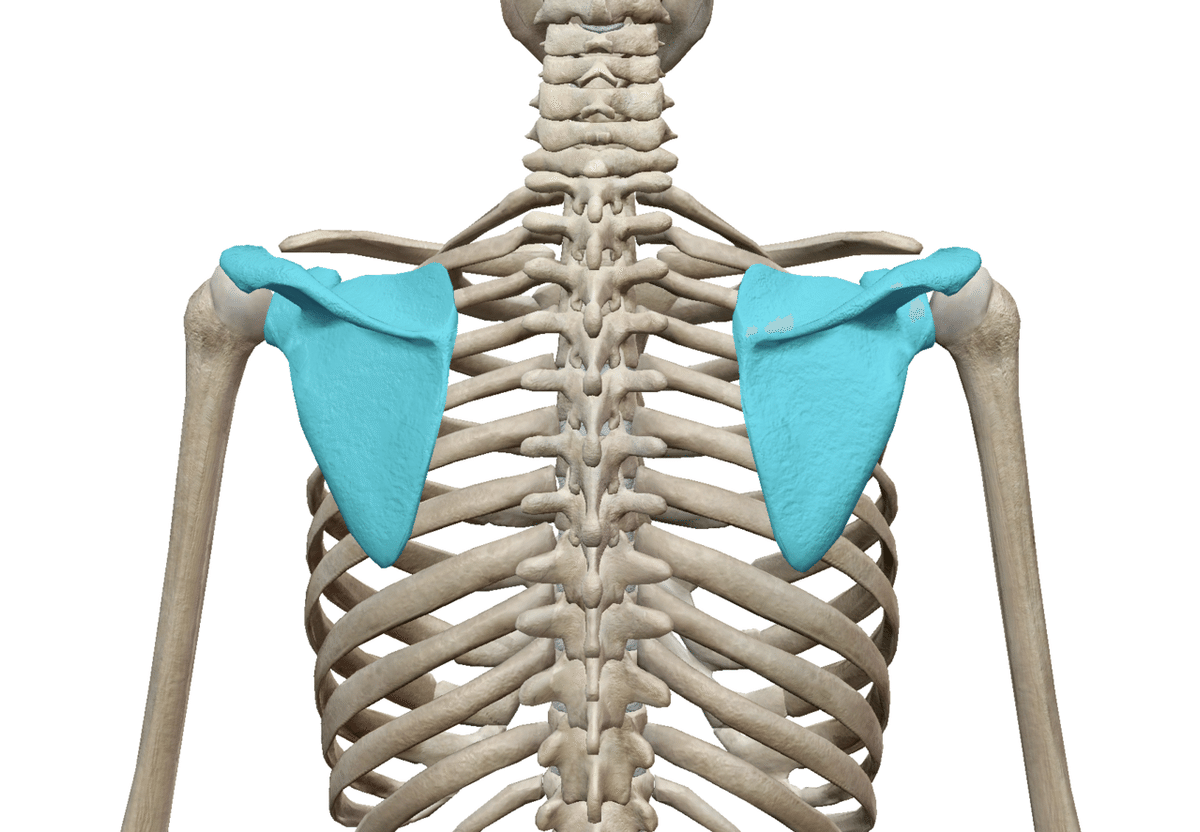

肩甲骨は背中に2つくっついている骨です。

肋骨との間に関節を形成しています。